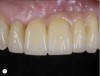

Fig 4. The retracted view reveals poor implant placement planning and restorative design.

Figure 4

Fig 5. Removal of the restoration further reveals improper implant position from mesial, buccal, lingual, coronal, and angulation perspectives.

Figure 5